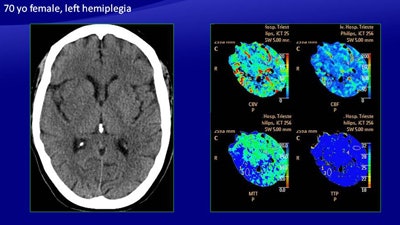

In a 70-year-old woman with left hemiplegia, CT (above) shows a slight hypodensity in the right basal ganglia, a large area of increased MTT, and a smaller area of reduced CBV and CBF. The automatically generated color map depict a large area of ischemic penumbra and a smaller area of infarcted core, which was confirmed on follow-up CT (below). All images courtesy of Dr. Maja Ukmar.

In a 70-year-old woman with left hemiplegia, CT (above) shows a slight hypodensity in the right basal ganglia, a large area of increased MTT, and a smaller area of reduced CBV and CBF. The automatically generated color map depict a large area of ischemic penumbra and a smaller area of infarcted core, which was confirmed on follow-up CT (below). All images courtesy of Dr. Maja Ukmar.As for the automatically generated maps, among the 19 patients with follow-up CT, seven had no perfusion abnormalities (two true negatives, five false negatives), while 12 patients had perfusion abnormalities. There were 25 areas of perfusion deficit: 15 were compatible with ischemic penumbra and 10 were compatible with infarcted tissue, with a total of 12 true-positive cases.